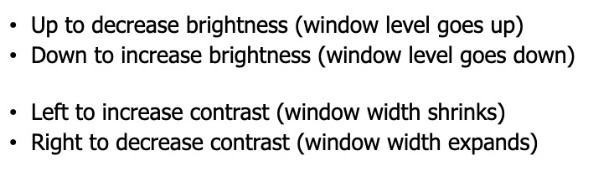

下面这张图表示出了两组对应概念之间的一些联系: